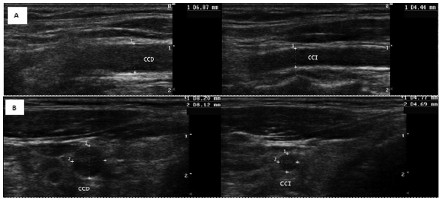

Presentamos el caso de un paciente de 49 años con agenesia renal izquierda, en seguimiento por hipertensión arterial e hipertrigliceridemia, con adecuado control de sus factores de riesgo a excepción del peso, manteniéndose con obesidad de grado I (IMC 32). Pese a lo antedicho, comenzó a presentar cifras en ascenso de creatinina (1,87 mg/ dl, con filtrado glomerular por fórmula de Cockcroft-Gault de 64 ml/ min y 41,3 ml/ min/ 1,73 m² por CKD-EPI) y micro albuminuria (68 mg/ 24 horas). En este contexto, con la intención de estudiar la existencia enfermedad vascular asociada, se le realizó un Eco doppler arterial de vasos del cuello, con los siguientes hallazgos (Figura 1):

Panel A eje largo de la arteria carótida común. Panel B eje corto del mismo vaso. Nótese, a la derecha de la imagen, la arteria carótida común izquierda (CCI), es hipoplásica, mide en el eje corto 4,7 mm anteroposterior (AP) y 4,6 mm en su diámetro transverso (T) mm, la carótida común contralateral (CCD) 8,2 mm AP y 8,1 mm T.